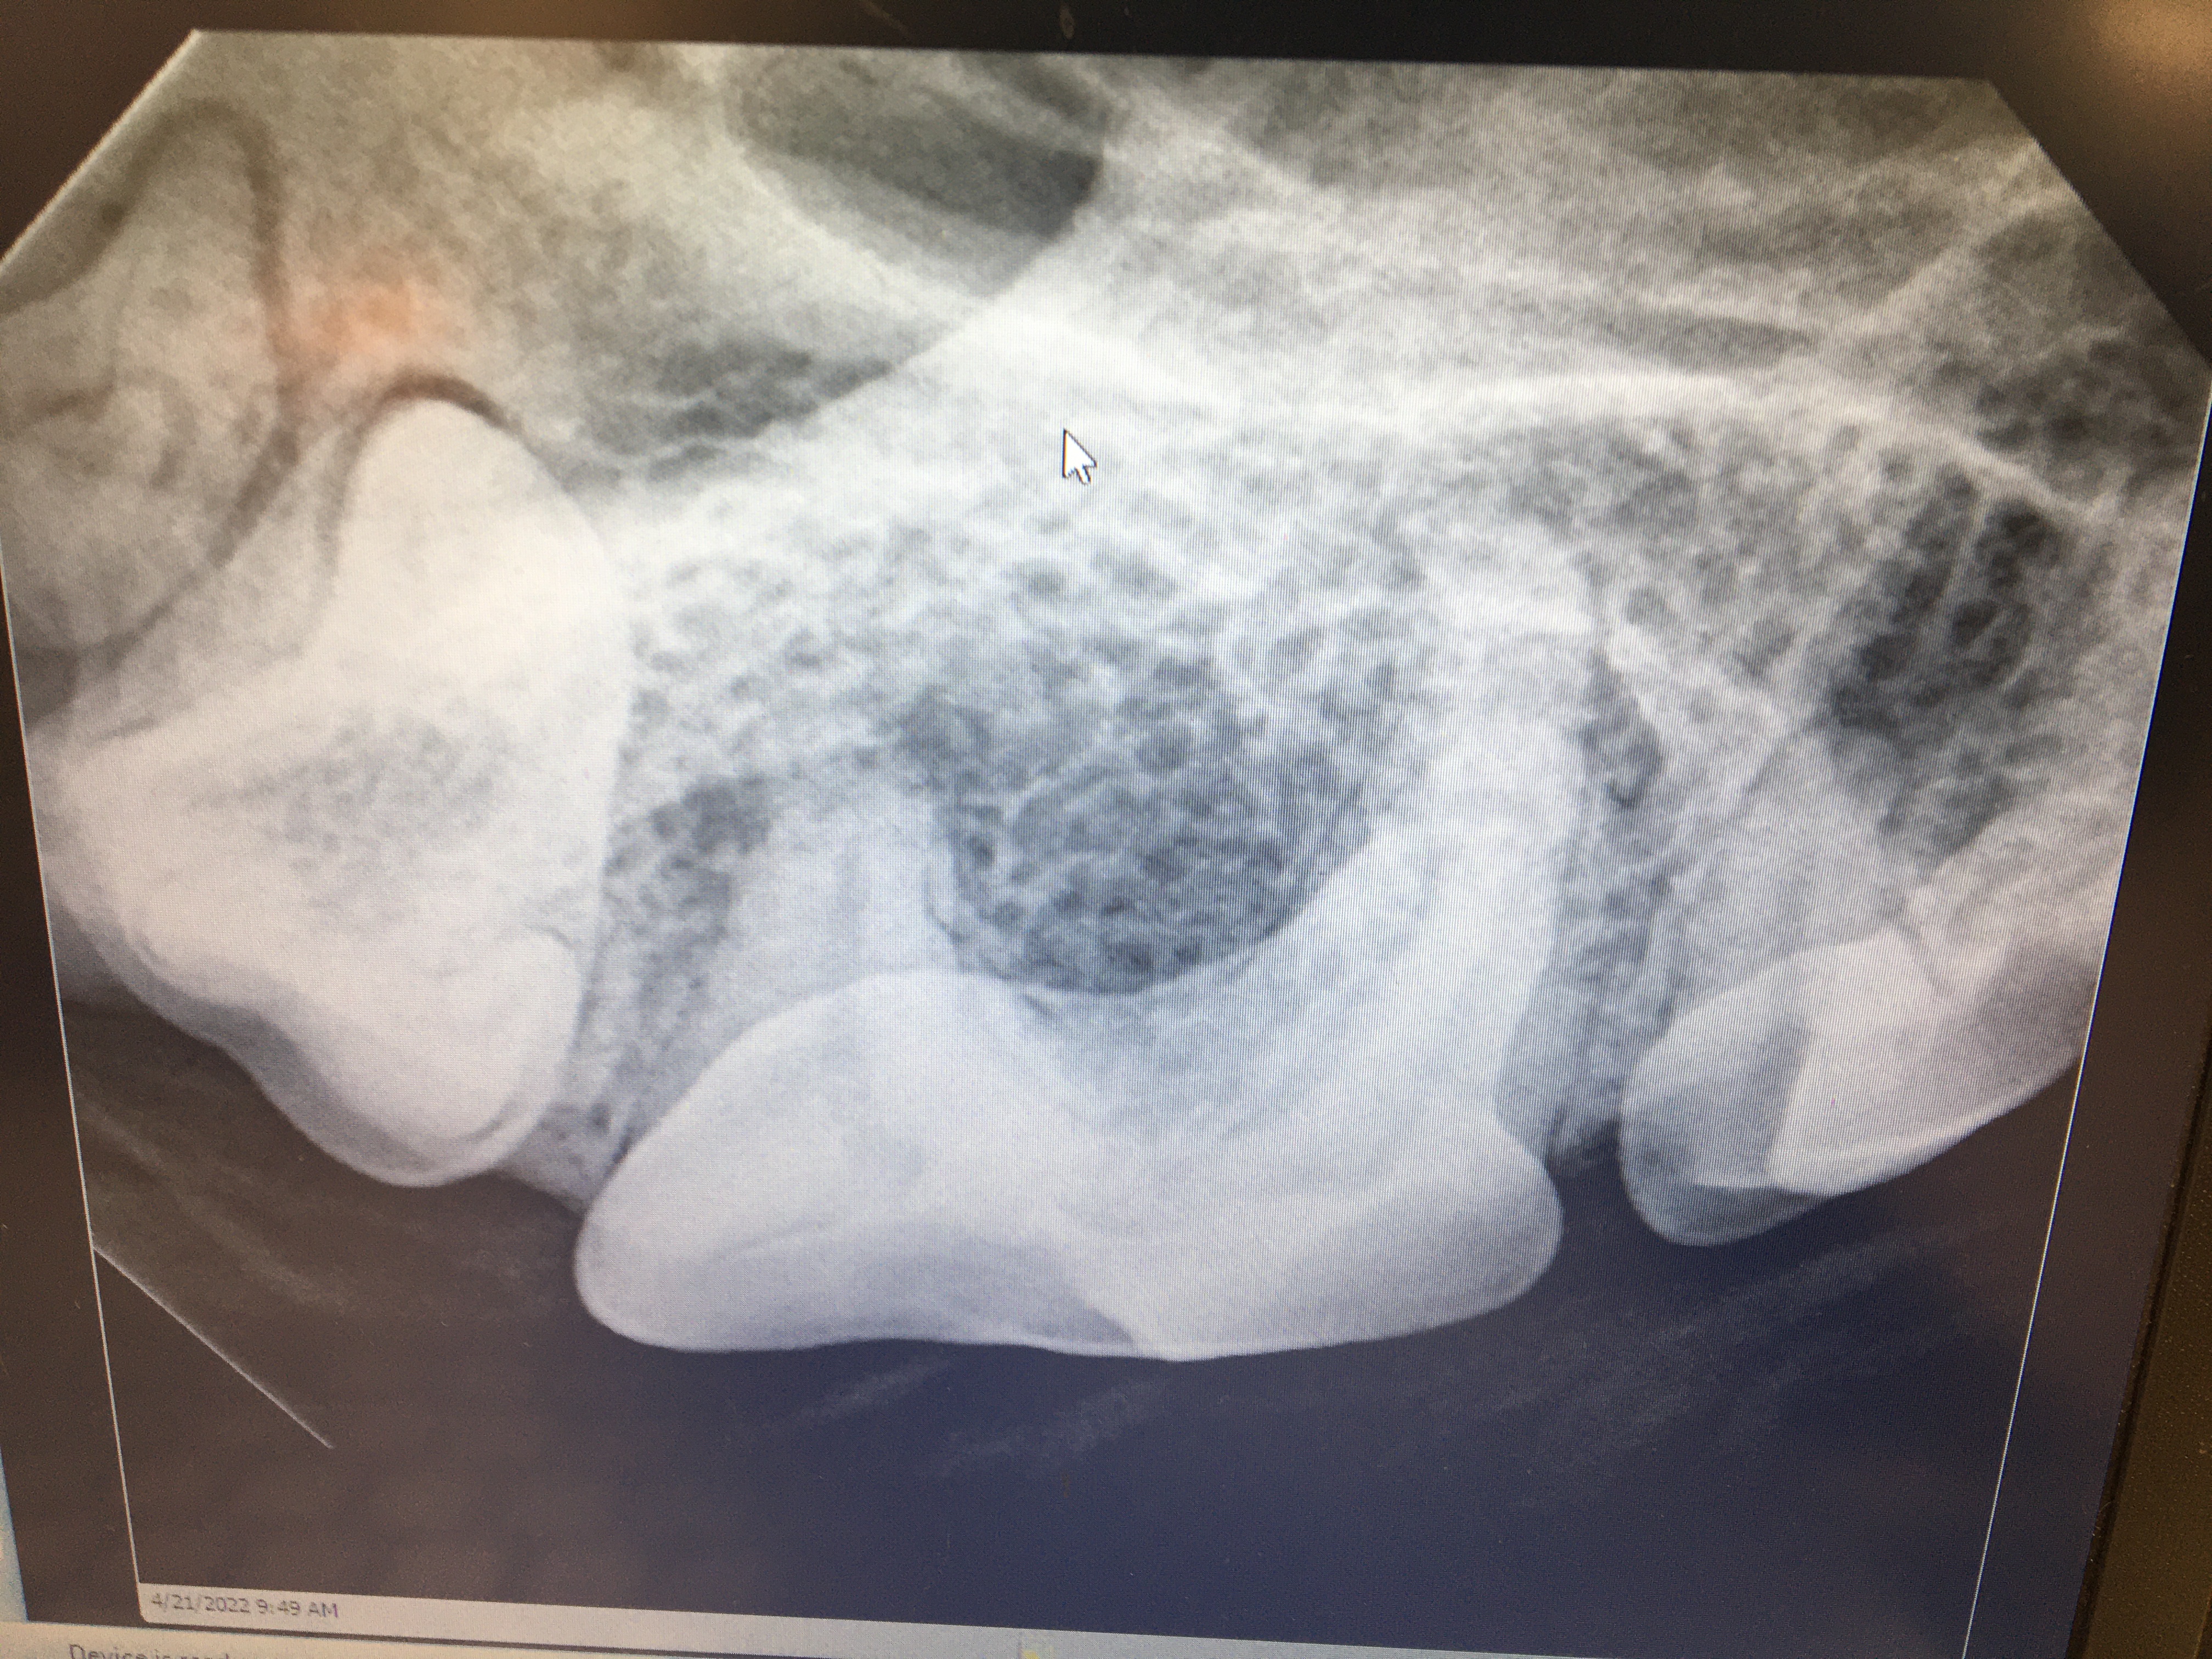

Feline Odontoclastic Resorptive Lesions

Felines exhibit a unique erosion at the cervical area called Feline Odontic Resorptive Lesions. These lesions appear to be associated with localized gingivitis. Many people have tried to explain why these lesions develop, however no one has come up with a definitive etiology.

I have restored FORL lesions with silver amalgam with excellent long term effect in multiple feline species. The lesions have ceased to enlarge. Restoration attempts with composite resin will fail, erosion will continue. Regrettably, most dentists and veterinary dentists will no longer have silver amalgam and the necessary instruments available to use it.

In personal conversations with Dr. Thomas Clark at Louisville Zoo I learned that he also has had success with silver amalgam. The lesion must be prepared with inverted cone burs to establish mechanical retention. These restorations have held up without failure for many years, see photos.